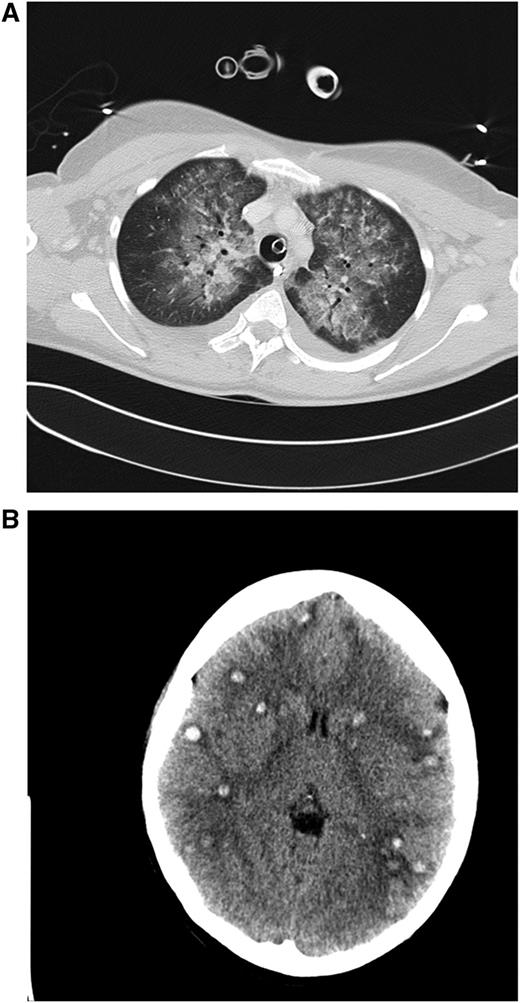

Clinical case 1. A 42-year-old woman presented to her general practitioner with general weakness and tooth pain. Laboratory assessment showed a WBC count of 80 000/µL, hemoglobin of 6.4 mg/dL, and platelet count of 21 000/µL, which led her physician to make an immediate referral to the local hospital, where a differential blood count revealed 56% myeloid blasts. By that time, the patient was in stable clinical condition with a minimally elevated C-reactive protein of 20 mg/L. She was put on 4 g hydroxyurea (HU) and planned for transferal to our hospital the next morning. During the night, she developed dyspnea requiring oxygen supply. We diagnosed an AML M4eo with inv(16) and started induction treatment with cytarabine plus daunorubicin (7 + 3) at a WBC count of 70 000/µL. Immediate leukapheresis was not possible because of the progressive dyspnea and the increasingly deranged coagulation status. By the next day, the WBC count had gone down to 19 000/µL, but the patient developed respiratory failure requiring mechanical ventilation. The computed tomography (CT) scan result was highly suggestive for leukostasis of the lungs (A), and cranial CT showed multiple focal supratentorial hemorrhages (B). During the next few days, respiratory indices improved, and the patient could be extubated. Early bone marrow response assessment showed a good response with leukemia-free hypoplastic marrow, and after regeneration of peripheral counts, a complete remission (CR) was diagnosed. The patient has currently completed consolidation chemotherapy and is in ongoing CR. The remarkable aspects of this case are (1) the fact that leukostasis developed rapidly even at a WBC count below 100 000/µL, possibly because of the monocytic nature of blasts11 ; (2) cytarabine alone led to a profound and rapid WBC reduction; and (3) the patient recovered from mechanical ventilation because the underlying leukostasis could be treated successfully. (A) Contrast-enhanced CT image (lung window) through the upper fields of the lungs demonstrates parenchymal infiltrates as well as diffuse ground-glass opacities suggestive for leukostasis and myeloblast infiltration. There is sparing of the lung periphery. Note also bilateral pleural effusions. Respiratory failure required mechanical ventilation support as indicated by the endotracheal tube. A central venous catheter in the right brachiocephalic vein and nasogastric tube in the esophagus can be seen. (B) Horizontal plane of native cranial CT scan demonstrating multiple hyperdense lesions in both brain hemispheres indicating hemorrhagic lesions. Accompanying cerebral edema is characterized by loss of gray-white matter differentiation, compression of lateral ventricles, and effacement of sulcal spaces.

Leukostasis refers to clinical symptoms and complications caused by HL. Whereas pathologically, the definition of leukostasis is clear (Figure 4), the clinical diagnosis is rarely made with high confidence.43 Leukostasis is empirically diagnosed when patients present with acute leukemia, HL, and respiratory or neurologic symptoms. However, the clinical and radiographic manifestations of leukostasis are difficult to distinguish from those of common infections or hemorrhagic complications of acute leukemia.24 Novotny et al39 developed a score for the clinical probability of leukostasis, and Piccirillo et al40 showed a correlation between Novotny’s score and early death in the case of a score of 3 indicating highly probable leukostasis. Approximately 44% to 50% of AML patients with a WBC count >100 000/µL have a high probability of leukostasis based on clinical symptoms. Although less frequently, typical symptoms can also occur in patients with leukocytosis below 100 000/µL.39,40 Organs most frequently affected are lung, brain, and kidneys. In a study by Porcu et al, the proportions of patients with respective symptoms were 39%, 27%, and 14%.6 Similar frequencies were reported by other investigators.9,29,52 CT scan or MRI of the head may reveal intracranial hemorrhage (Figures 1 and 2). A chest radiograph or CT scan often will show bilateral interstitial or alveolar infiltrates (Figure 1).43,53 The typical clinical symptoms of leukostasis are listed in Table 1. Apart from tissue damage caused by stasis and leukocyte infiltration, hemorrhage and thromboembolic events are frequent and relevant complications of leukostasis. 9,19,43